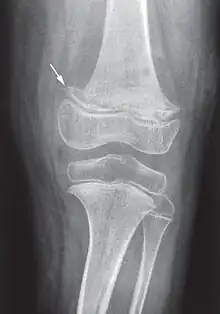

While many animals produce their own vitamin C, humans and a few others do not.[2] Vitamin C is an antioxidant, is required to make the building blocks for collagen, carnitine, and catecholamines, and assists the intestines in the absorption of iron from foods.[2][4][5] Diagnosis is typically based on outward appearance, X-rays, and improvement after treatment.[2]

Diagnosis is typically based on physical signs, X-rays, and improvement after treatment.[2]